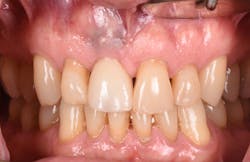

Figure 20: An osteotomy was done to access apical area of implant No. 8 utilizing the Er:YAG laser at 20 pps/70 mJ. The then-exposed area was irradiated using a combination of detoxification and biostimulation of the bone and implant to prepare the area to receive a bone graft.

Figure 21: After mechanical debridement and surface detoxification